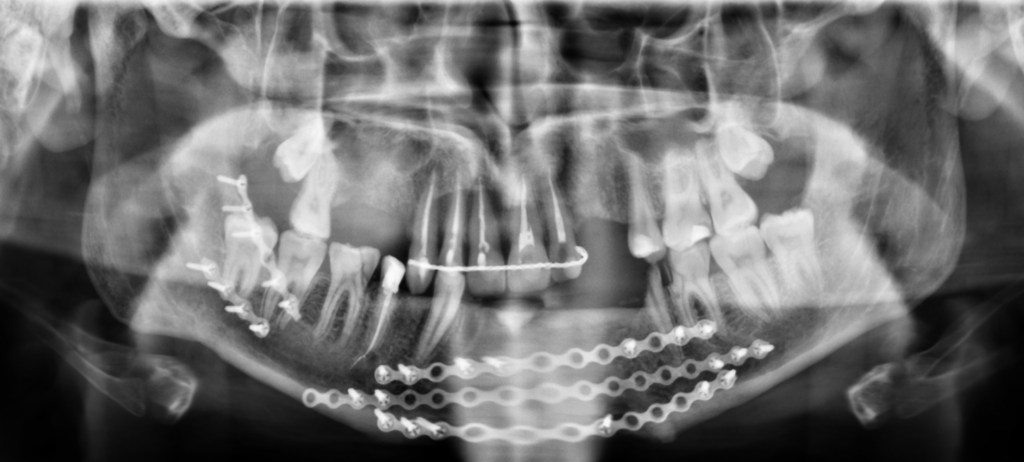

- utratę kilkunastu zębów

- wyłamanie wyrostka zębodołowego

- wieloodłamowe złamania żuchwy

- złamanie kości jarzmowej i szczęki

Wypadek spowodował, że oprócz przebytych dotąd operacji, konieczne jest usunięcie tymczasowych tytanowych płytek w szczęce i żuchwie, które miały na celu zespolenie połamanych kości, a w dalszej części kolidują z odbudową całego zniszczonego uzębienia. Usunięcie tytanowych płytek z kości żuchwy, oraz dodatkowa ekstrakcja sześciu złamanych zębów zostanie przeprowadzona w połowie lutego 2024 roku w szpitalu w Elblągu, gdzie trafiłem w dniu wypadku. Dalsza część leczenia, czyli odbudowa i rekonstrukcja uzębienia, niestety nie jest finansowana przez NFZ. Koszty związane z odbudową szczęki i żuchwy są ogromne, gdyż muszę uzupełnić bardzo dużo ubytków w uzębieniu, odbudować brakujące kości w celu wszczepienia implantów. Zabiegi te, mają na celu przywrócenie przede wszystkim funkcji gryzienia, mówienia oraz pełnego uśmiechu i pozbycia się wstydliwego dyskomfortu. Powyższe leczenie wiąże się z wieloma wizytami u stomatologa, ortodonty, protetyka, chirurga, dlatego konieczne były kolejne konsultacje w wyspecjalizowanych w tym zakresie klinikach w Warszawie, Gdańsku i Gdyni, które są w stanie podjąć się tak trudnego przypadku, gdzie można rzec „wszystko” jest do gruntownej odbudowy.

Niestety jak twierdzi wielu specjalistów jest to bardzo trudny przypadek i wymaga kompleksowej odbudowy kości żuchwy i praktycznie całkowitego uzębienia – łącznie 21 zębów, 10 implantów. Wstępnie szacuje się (po wizytach w kilku klinikach), że zabiegi związane z konieczną stomatologią, ortodoncją, chirurgią, implantologią, protektyką i późniejszą rehabilitacją szczękową wyniosą blisko 150 tysięcy zł. Choć kwota zwala z nóg to cieszę się, że może już pod koniec wakacji będę mógł prawdziwie się uśmiechać i znów spróbować soczystego jabłka!